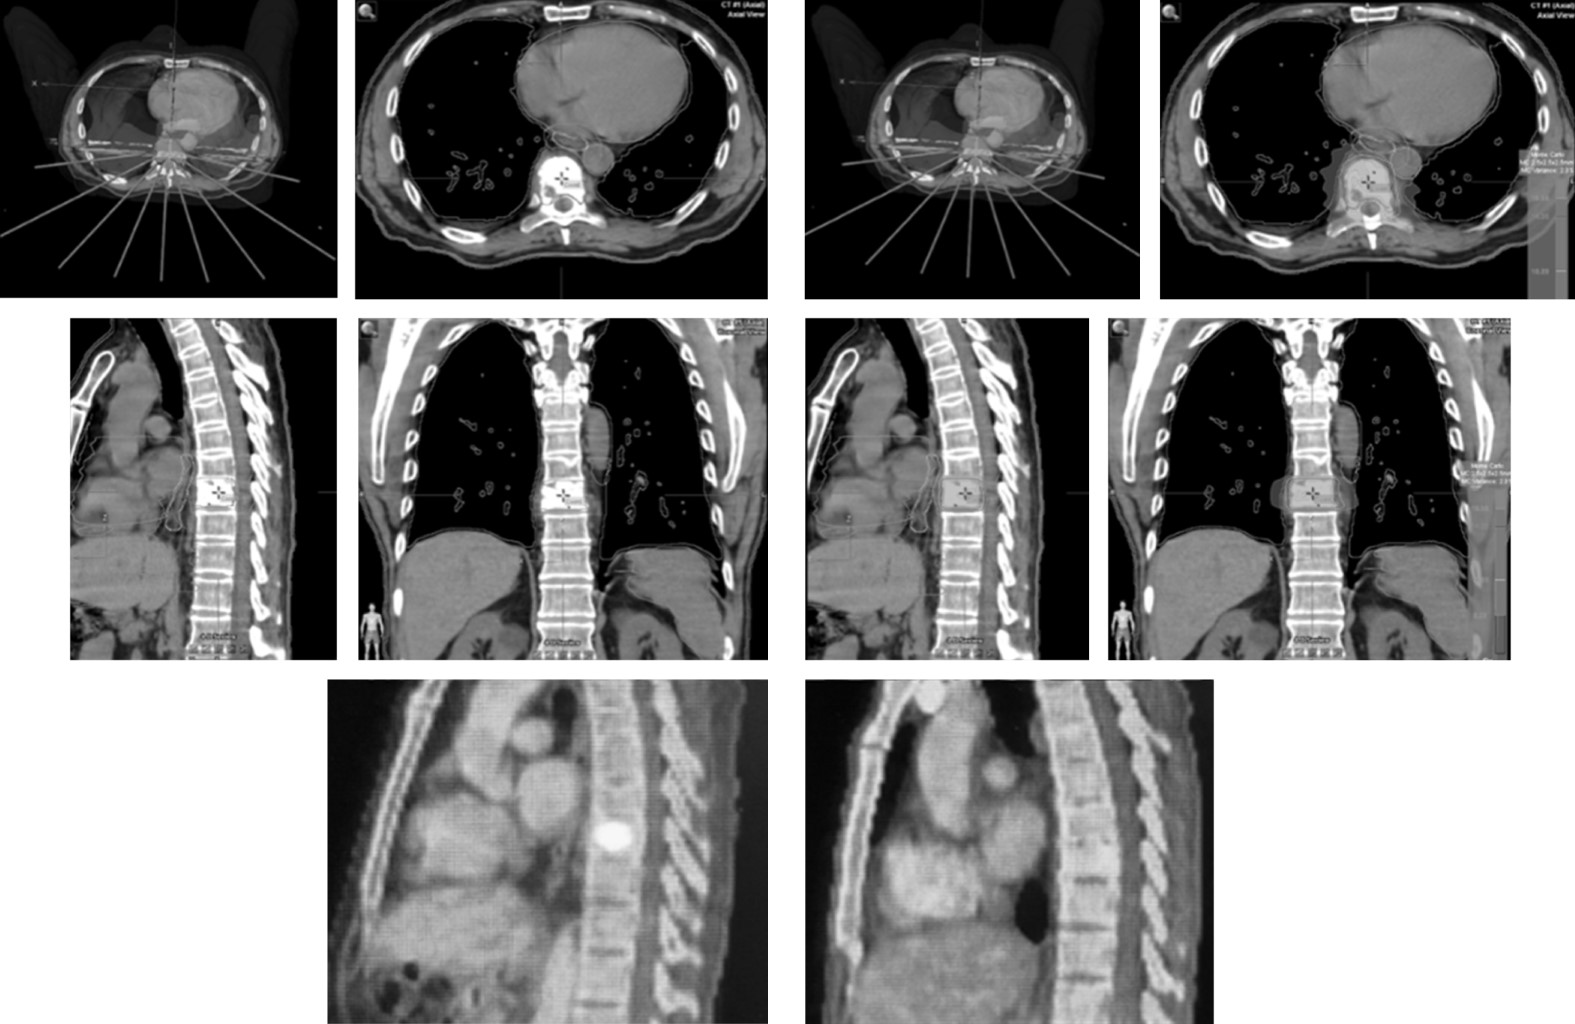

En México existen hospitales públicos y privados que realizan radiocirugía con muy buenos resultados;10 sin embargo, el Centro Médico ABC fue el primero en iniciar un programa de radiocirugía extracraneal incluyendo columna, pero también otros órganos como pulmón, hígado y próstata, entre otros (Figura 6).

Después de un largo esfuerzo conjunto entre el Centro Neurológico y el Centro de Cáncer del Centro Médico ABC, se logró adquirir un equipo de última generación para dar tratamientos con radiocirugía tanto craneal como extracraneal. El equipo es un acelerador lineal de 6 MV Novalis Tx-Varian (Brainlab, GmbH Germany) con sistema de colimación micromultihojas y de conos. Se logró conjuntar un equipo multidisciplinario conformado por físicos médicos, radiooncólogos y neurocirujanos, todos con una formación sólida en el campo de la radiocirugía y con experiencia previa.

El primer tratamiento se realizó el 12 de noviembre del 2012 a una paciente con una metástasis cerebral por cáncer de mama con un buen control de la enfermedad local.

Desde el inicio de su funcionamiento y hasta el 28 de junio de 2019 se habían tratado un total de 867 casos. De éstos, 451 (52%) fueron tratados con radioterapia, 286 (33%) con radiocirugía craneal y 130 (15%) con radiocirugía extracraneal; cada año hemos logrado tener un mayor número de tratamientos. Las patologías más frecuentemente atendidas fueron: neoplasias 820 (95%), vascular 37 (4%) y funcional nueve (1%). De la patología neoplásica 689 (80%) fueron malignos y 131 (15%) benignos considerando el total de tratamientos. En la Figura 7 se observan ejemplos de pacientes tratados en la Unidad de Radiocirugía del Centro Médico ABC.